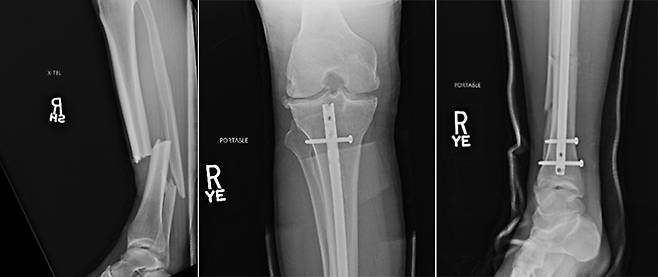

실바가 강하게 찬 로킥이 크리스 와이드먼(36, 미국)이 방어하려고 세운 무릎에 딱 걸렸다. 순간 왼쪽 정강이가 완전히 부러져 버렸다.

사람의 정강이에는 정강뼈와 종아리뼈가 있다. 실바와 와이드먼 모두 두 뼈가 복합 골절된 경우로, 뼈가 붙는 데 오랜 시간이 걸릴 뿐 아니라 빠진 근육을 붙이고 제대로 훈련을 재개하려면 더 시간이 필요하다.